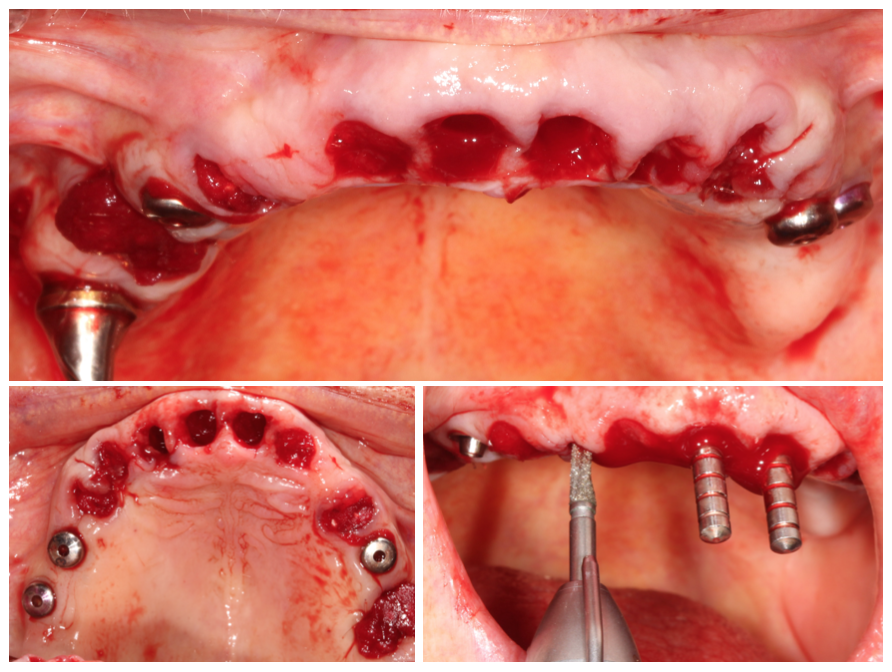

Le projet chirurgical permet d’envisager d’extraire l’ensemble des dents maxillaires et de placer six implants entre 15 et 25 pour la réalisation d’un bridge transvissé de 12 éléments :

La pose des implants devra (et pourra) être précédée d’une résection osseuse verticale suffisante après les extractions afin de remonter la ligne de transition implanto-prothétique à la limite du découvrement de la lèvre pour assurer un sourire plus esthétique. C’est ce dernier point qui décide la patiente à accepter ce plan de traitement de restauration globale.

Dans ce cas, la pose des implants a été réalisée sans guide chirurgical : ce sont les alvéoles déshabitées qui ont guidé les forages.

Radio de contrôle post-opératoire (les alvéoles ont été comblées par os autogène et BioOs) :

Notez que l’axe des implants distaux a permis d’éviter les sinus pour une simplification du protocole chirurgical

Vue clinique en fin de chirurgie des implants recouverts de piliers coniques :

Les piliers sont alors coiffés par des transferts pour enregistrement numérique (scanbodies) :